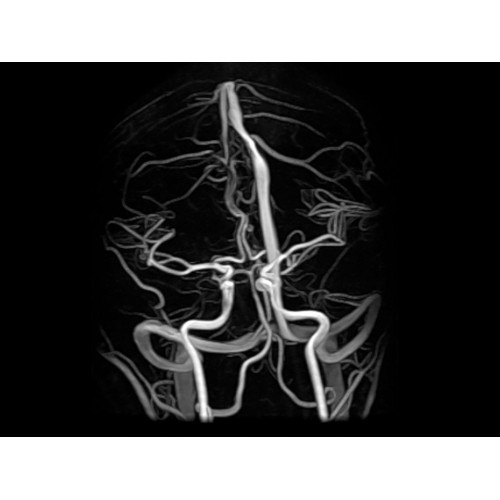

МР-ангиография Да

Благодаря принципиально новым технологиям мы расширили возможности МР-томографов с широкими туннелями, совместив непревзойденное качество изображений с высокой производительностью при широком — 50 см — поле зрения.

МР-томограф Optima MR450w позволяет получать изображения исключительно высокого качества, которые помогают установить диагноз. Чтобы удовлетворить ожидания клиентов в отношении высокого качества, в МР-томографе Optima MR450w были сохранены дополнительные возможности платформы Discoverу, привнесшие в его работу универсальность и мощь.